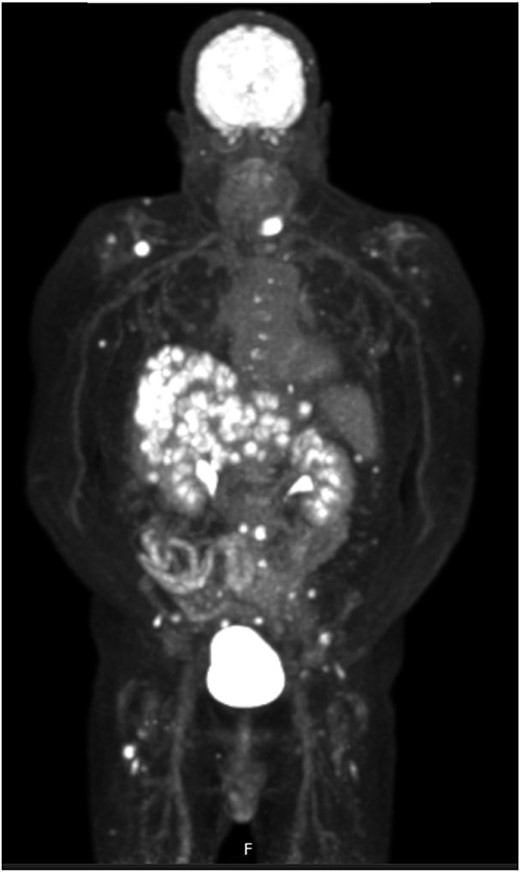

Post-review, he was listed for an urgent biopsy under local anaesthetic. Histology showed well-to-moderately differentiated adenocarcinoma, with the likely primary being upper gastrointestinal or pancreatic in origin. Positive immunostaining was noted for CK7 and negative for p63, TTF-1, Napsin, CK20 and PSA. Magnetic resonance imaging (MRI) of the face and neck showed a 2.6-cm lesion on the chin invading subcutaneous tissues, with no mandibular involvement (Fig. 1). Due to the nature of the histology results, he underwent a positron emission tomography(PET)-computed tomography (CT) scan, which showed a cystic area in the pancreatic tail, alluding to a pancreatic adenocarcinoma primary. Widespread metastases noted included multifocal liver metastases, peritoneal lymph node, muscle and bony involvement (Figs 2–4).